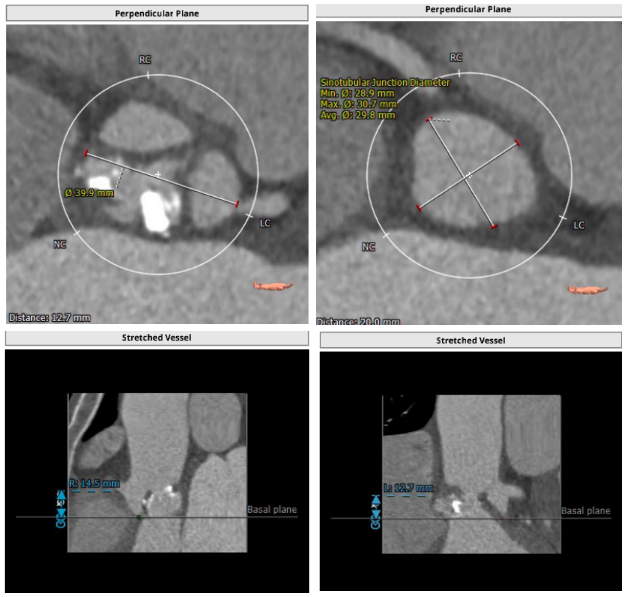

解剖结构

主动脉根部解剖:

血管入路解剖: